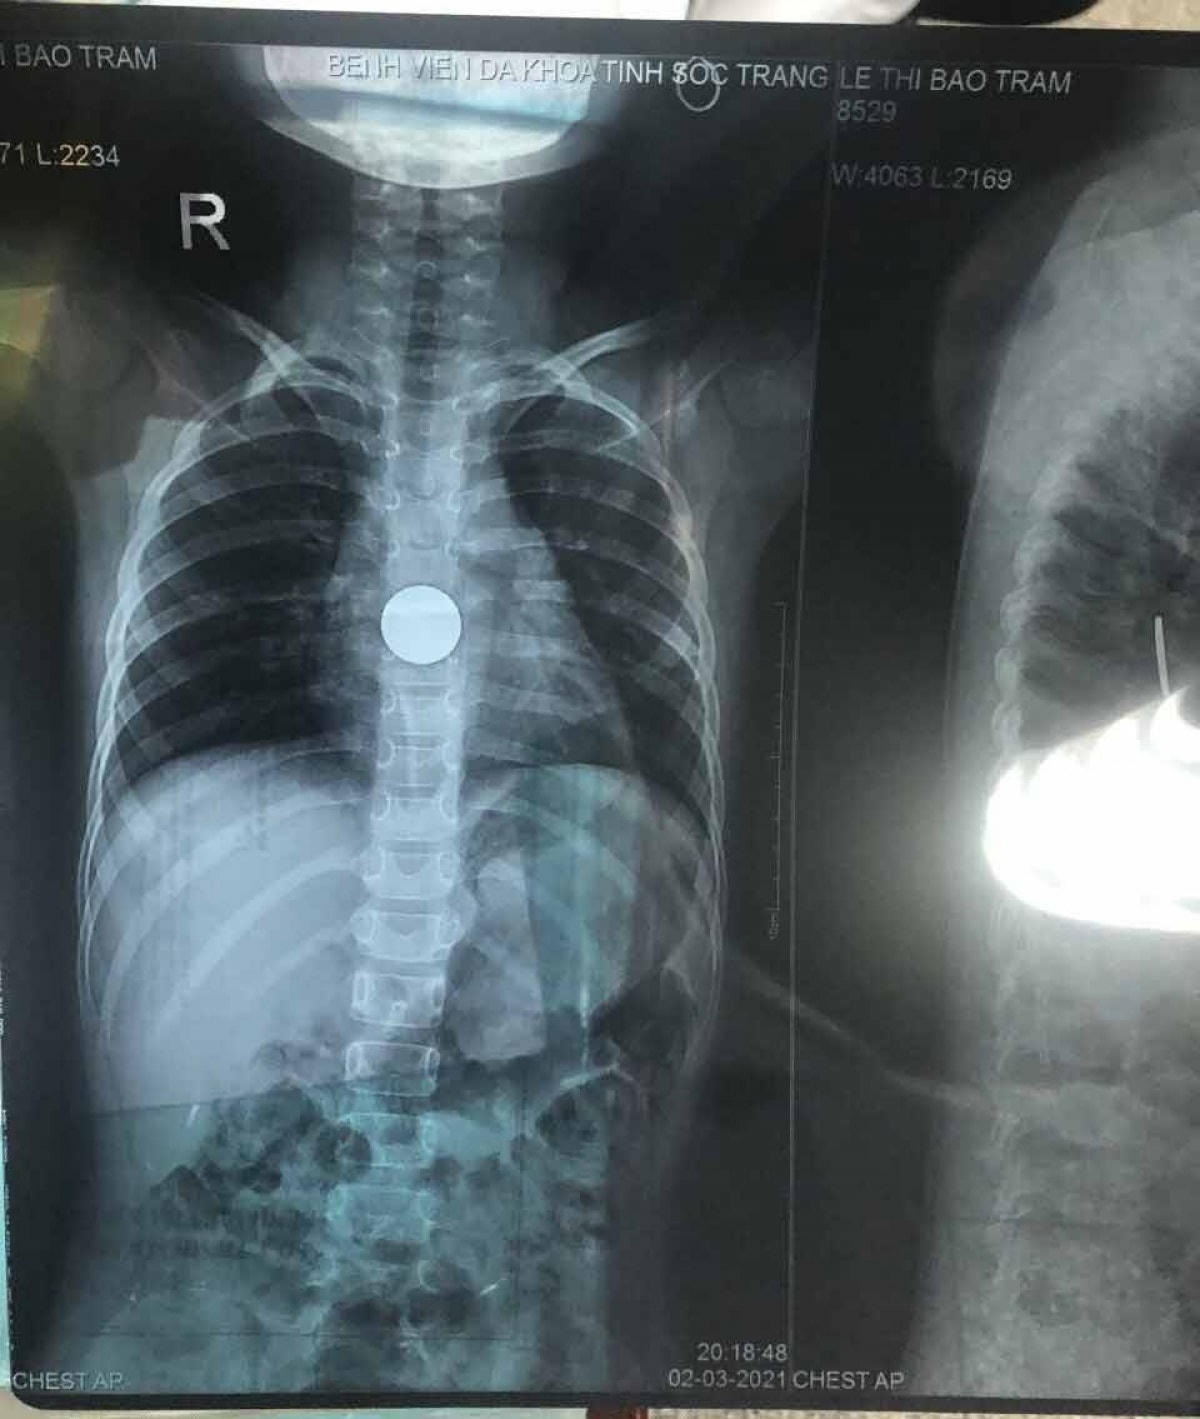

Qua hình ảnh X-Quang, dị vật được xác định là đồng xu, đang kẹt ở vị trí cách cung hàm trên 25 – 26cm, rất gần với dạ dày. Đây là một trường hợp rất khẩn cấp, nếu không kịp thời gắp dị vật, có thể dị vật sẽ gây ra tình trạng tắt ruột. Y bác sĩ Khoa Tai Mũi Họng tiến hành nội soi gây mê và đã gắp thành công dị vật cho bé T. Hiện tại, tình trạng sức khỏe của bé ổn, khỏe mạnh, vui chơi bình thường và có thể xuất viện trong chiều nay 3/3.